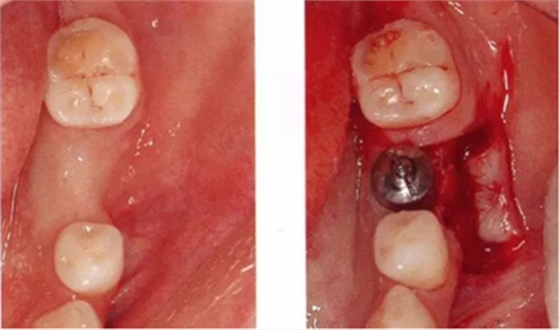

▲圖6-1

頰側角化齦較少,頰系帶高位附著。

▲圖6-4,5

圖6-4 第二次手術前的(牙合)面照。牙槽嵴頂?shù)缴鄠戎g有一定程度的角化齦,但是頰側有凹陷,在這種狀態(tài)下進行治療,會遺留牙槽嵴形態(tài)異常的問題。

圖6-5 一定程度上保留了舌側的角化齦,頰側使用內斜(從舌側向頰側)切開的方式,從舌側切開牙槽嵴的角化齦,形成半厚瓣。